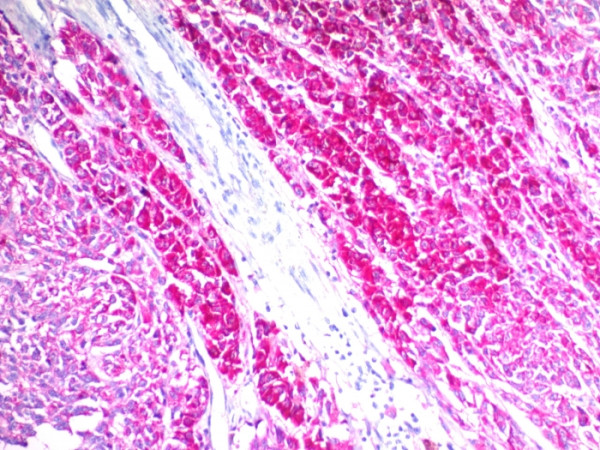

Product information "Anti-CD63 (Late Endosomes Marker), clone SPM524"

Formulation: Purified Ab with BSA and Azide at 200ug/ml. Cellular Localization: Cell membrane, Cell surface, Cytoplasm, Endosome, Extracellular exosome, Late endosome membrane, Lysosome membrane, Melanosome, Multivesicular body, Secreted. Positive Control: SK-MEL-28, UM87MG or MCF-7 cells. Human melanoma or spleen. Chromosome Location: 12q13.2. Protein Function: Functions as a cell surface receptor for TIMP1 and plays a role in the activation of cellular signaling cascades. Plays a role in the activation of ITGB1 and integrin signaling, leading to the activation of AKT, FAK/PTK2 and MAP kinases. Promotes cell survival, reorganization of the actin cytoskeleton, cell adhesion, spreading and migration, via its role in the activation of AKT and FAK/PTK2. Plays a role in VEGFA signaling via its role in regulating the internalization of KDR/VEGFR2. Plays a role in intracellular vesicular transport processes, and is required for normal trafficking of the PMEL luminal domain that is essential for the development and maturation of melanocytes. Plays a role in the adhesion of leukocytes onto endothelial cells via its role in the regulation of SELP trafficking. May play a role in mast cell degranulation in response to Ms4a2/FceRI stimulation, but not in mast cell degranulation in response to other stimuli [The Uniprot Consortium]

| Application: | FC, IF, IHC |